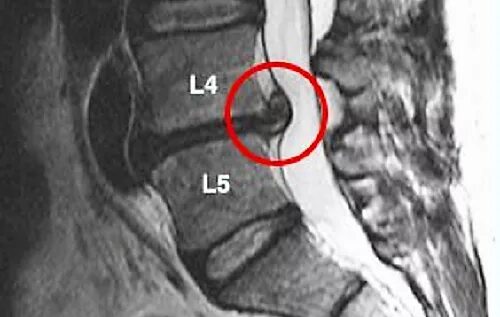

Грыжа 4 5